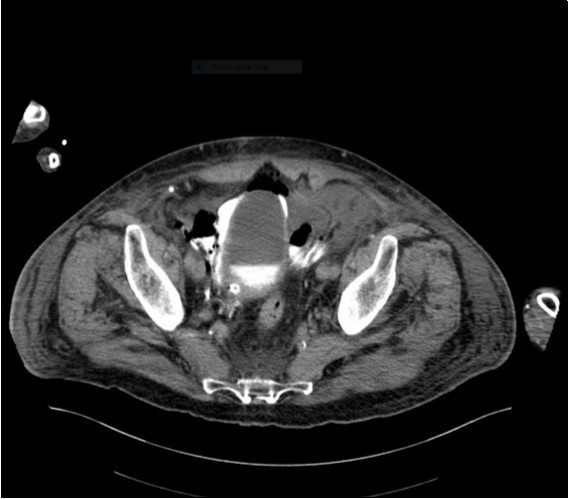

An urgent CT abdomen revealed a bladder perforation with the tip of the irrigating catheter situated in the abdominal cavity (Figure 1, Figure 2, Figure 3a,Figure 3b). This was most likely due to over-insertion of the 3-way catheter due to the extra force required because of the benign prostatic hypertrophy. He had therefore been receiving normal saline as ‘peritoneal dialysis’ with normal saline since insertion of the catheter. The catheter was withdrawn, and the patient made a full recovery.

Figure 2.coronal plane CT image

coronal plane CT image